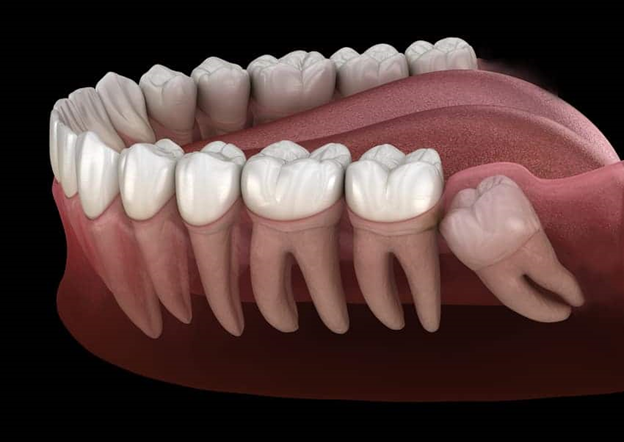

Các vị trí mọc bất thường của răng khôn

Răng khôn không phải lúc nào cũng mọc thẳng và đủ chỗ. Một số trường hợp phổ biến gồm:

- Răng khôn mọc lệch

- Hướng mọc lệch ra má hoặc vào trong.

- Nếu không gây sưng đau hay viêm lợi, có thể chưa cần nhổ.

- Răng khôn mọc kẹt

- Cung hàm không đủ khoảng trống, chỉ một phần thân răng mọc lên.

- Thường gây sưng, đau, viêm nướu hoặc lợi trùm.

- Răng khôn mọc ngầm

- Toàn bộ răng nằm trong xương hàm, có thể đâm ngang hoặc chèn vào răng số 7 bên cạnh.